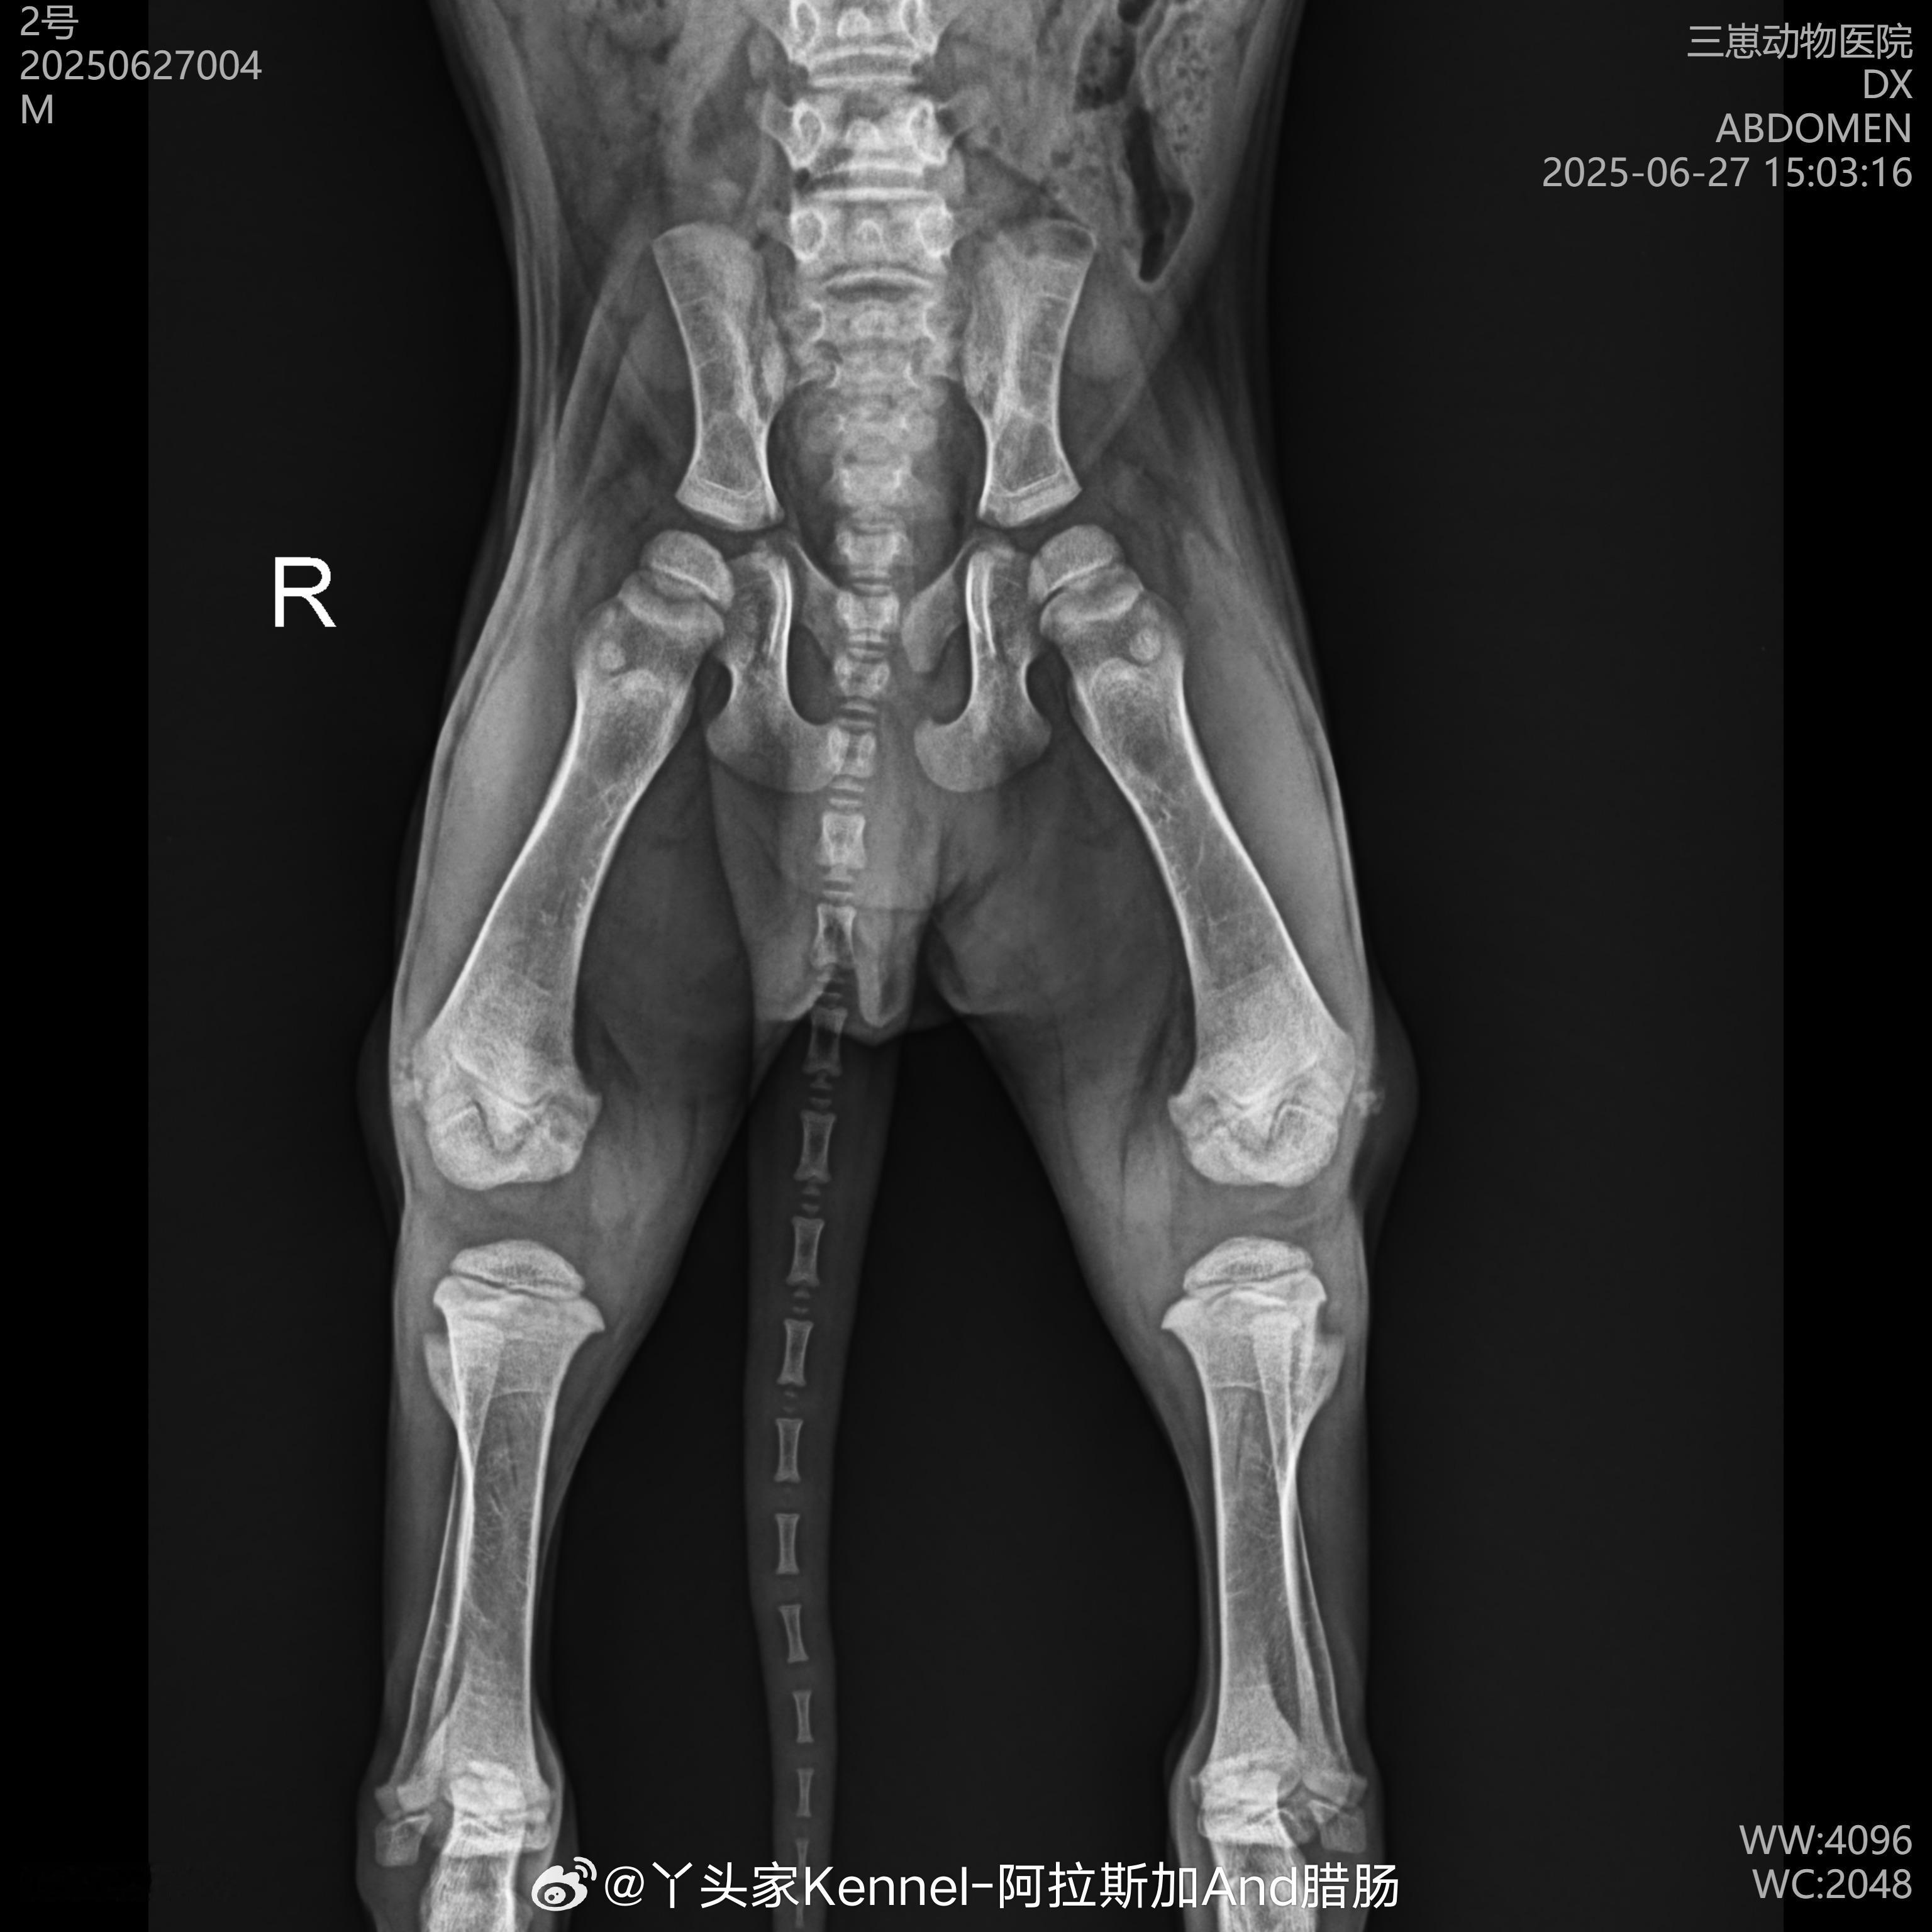

阿拉斯加幼犬新家前体检全记录!:每只阿拉斯加去新家前都会做全身体检,连髋关节X光都安排上了,比人类宝宝还细致~检查过程:医生仔细给小家伙做各项检查,包括抽血时的小紧张,全程温柔安抚,小家伙瞪人也像在撒娇~2 健康保障:从血常规到髋关节,每一项都严格把关,确保狗狗健康抵达新家,当妈的终于放心了~3 后续观察:回家后医生还会叮嘱注意事项阿拉斯加萌宠